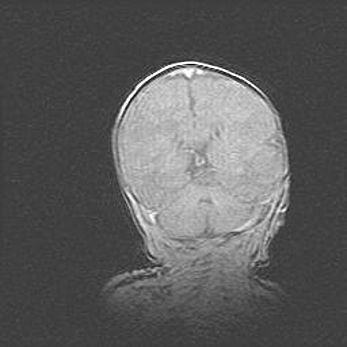

Открытая гидроцефалия.

Возраст: 6 месяцев 15 дней

Вес: 6200 г

Пол: женский

Окружность головы: 41 см

Срок гестации: 38 недель

Гидроцефалия головного мозга у новорожденных – это скопление избыточного количества цереброспинальной жидкости в головном мозге. Ее избыточное скопление в мозге приводит к патологическому расширению желудочков мозга (четырех полостей, расположенных в глубине белого вещества мозга, заполненных цереброспинальной жидкостью и связанных узкими проходами).

Открытый тип гидроцефалии (сообщающаяся) наблюдается тогда, когда нарушен механизм всасывания ликвора в системный кровоток. При этом типе причиной заболевания чаще всего является перенесенные ранее инфекции (например: менингит),  либо же наличие крови в субарахноидальном пространстве.